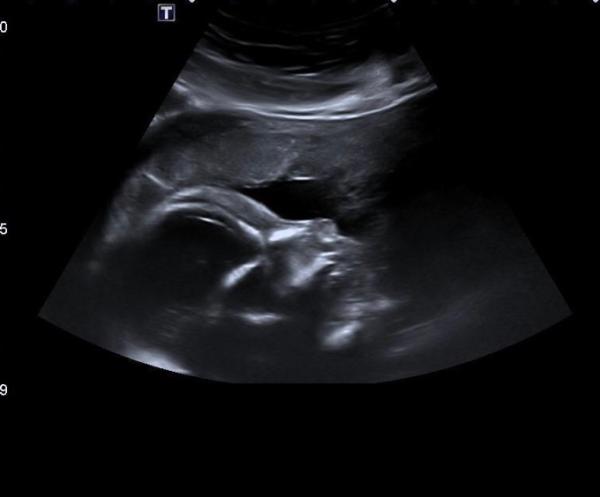

... und endlich gibt es Fotos von unserem störrischen kleinen Mann. Auch heute hat er es dem Pränataldoktor so schwer wie möglich gemacht, aber er hat sich Gott sei dank eine Dreiviertel Stunde Zeit genommen für den Schall. Das Allerwichtigste: Das Herz, das beim letzten Mal ja nicht gut darstellbar war und der Grund für die Überweisung ist tip top in Ordnung. Auch alle anderen Organe sind gut entwickelt. Bei 22+0 wiegt der kleine Mann jetzt 550g und ist 28cm groß. Arzt meinte das sei im oberen Normbereich. Ich freu mich so, dass ich endlich das erste Bild von ihm habe nach dem weißen Blob Liebe Grüße!

Bild zu Zurück von der Feindiagnostik.. - Forum für April - Mamis